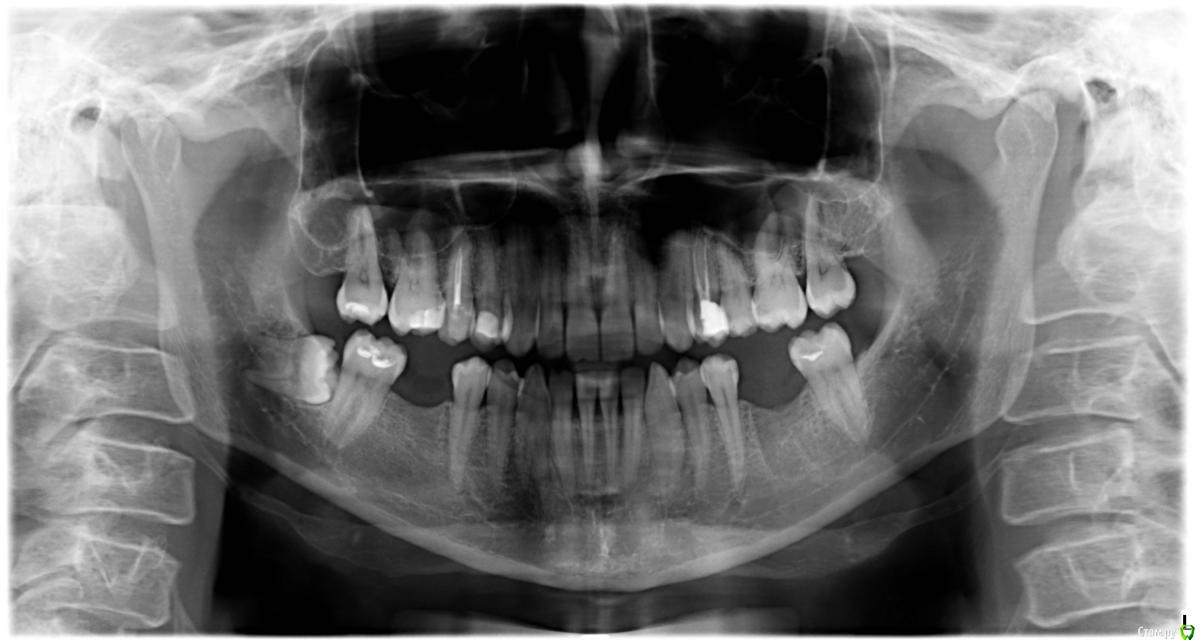

kamranchick Опубликовано 5 апреля, 2015 Поделиться Опубликовано 5 апреля, 2015 добрый день.Можно ли ортодонтически вытащить 8ой зуб на место 7, а 7ой на место 6гоИ будет ли потеря чувствительности после ретракции? судя по снимку травма будет значительная Ссылка на комментарий

Bier Опубликовано 6 апреля, 2015 Поделиться Опубликовано 6 апреля, 2015 почему? я думаю если задаст.целью то можно. А что не стоит это точно.подъедет полунаклоненный зуб с резорбированными корнями, через 3 года )) 6 Ссылка на комментарий

kamranchick Опубликовано 7 апреля, 2015 Автор Поделиться Опубликовано 7 апреля, 2015 Боюсь не справлюсь с таким удалением. скажу вам честно Ссылка на комментарий

kamranchick Опубликовано 7 апреля, 2015 Автор Поделиться Опубликовано 7 апреля, 2015 Сам работаю в поликлиннике, кроме долот элеваторов и щипцов ничего нет.Думаю попробую взять портативную машинку и вот такой план будетРезекция костного участка, распил коронки, потом с помощью долота разделить корни, помоему их там 3 и вытащить с помощью элеваторов.Какие будут комментарии? Ссылка на комментарий